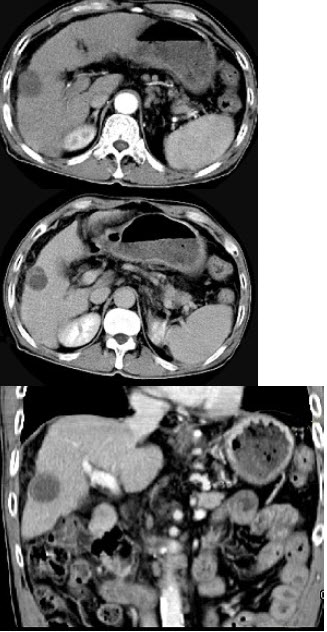

28、单项选择题

如图所示,溶组织内阿米巴原虫侵入肝脏最主要的途径是()

A.穿透结肠壁直接入肝

B.经胆道逆行入肝

C.经门静脉入肝

D.经肝静脉入肝

E.经局部淋巴管入肝